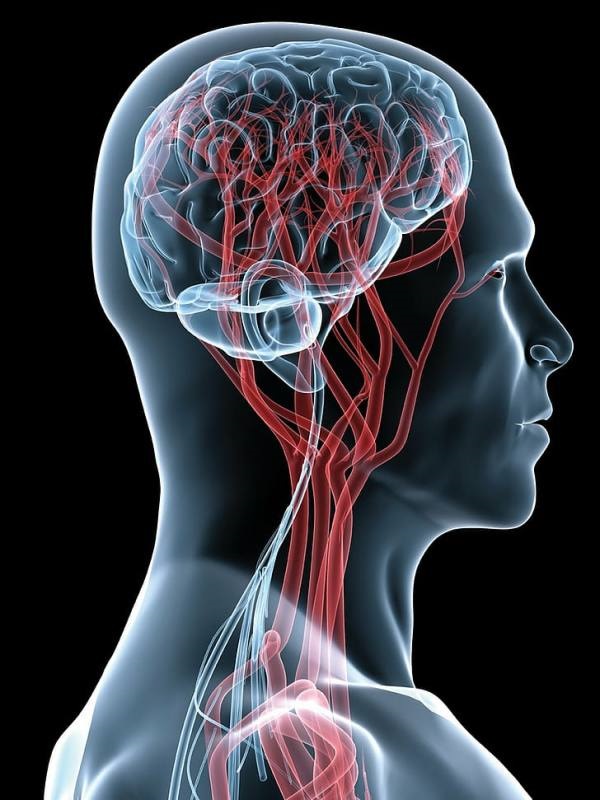

Vascular Neurosurgery

Vascular neurosurgery involves treating patients with disorders of the blood vessels in the brain and spine. This requires highly specialized neurosurgeons who have experience treating these disorders.